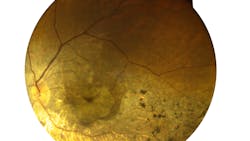

At the National Institutes of Health, a surgical team successfully implanted a patch of tissue made from patient cells with the goal of treating advanced “dry” age-related macular degeneration (AMD), also known as geographic atrophy. Dry AMD is a leading cause of vision loss among older Americans and currently has no treatment.

This surgery is the culmination of 10 years of research and development at the NEI. In the NIH lab, the patient’s blood cells were converted to iPS cells, which can become almost any type of cell in the body. In this case, they were programmed to become retinal pigment epithelial (RPE) cells, the type of cell that degenerates in the advanced forms of dry AMD. RPE cells nourish and support light-sensing photoreceptors in the retina. In AMD, the loss of RPE leads to the loss of photoreceptors, which causes vision loss.